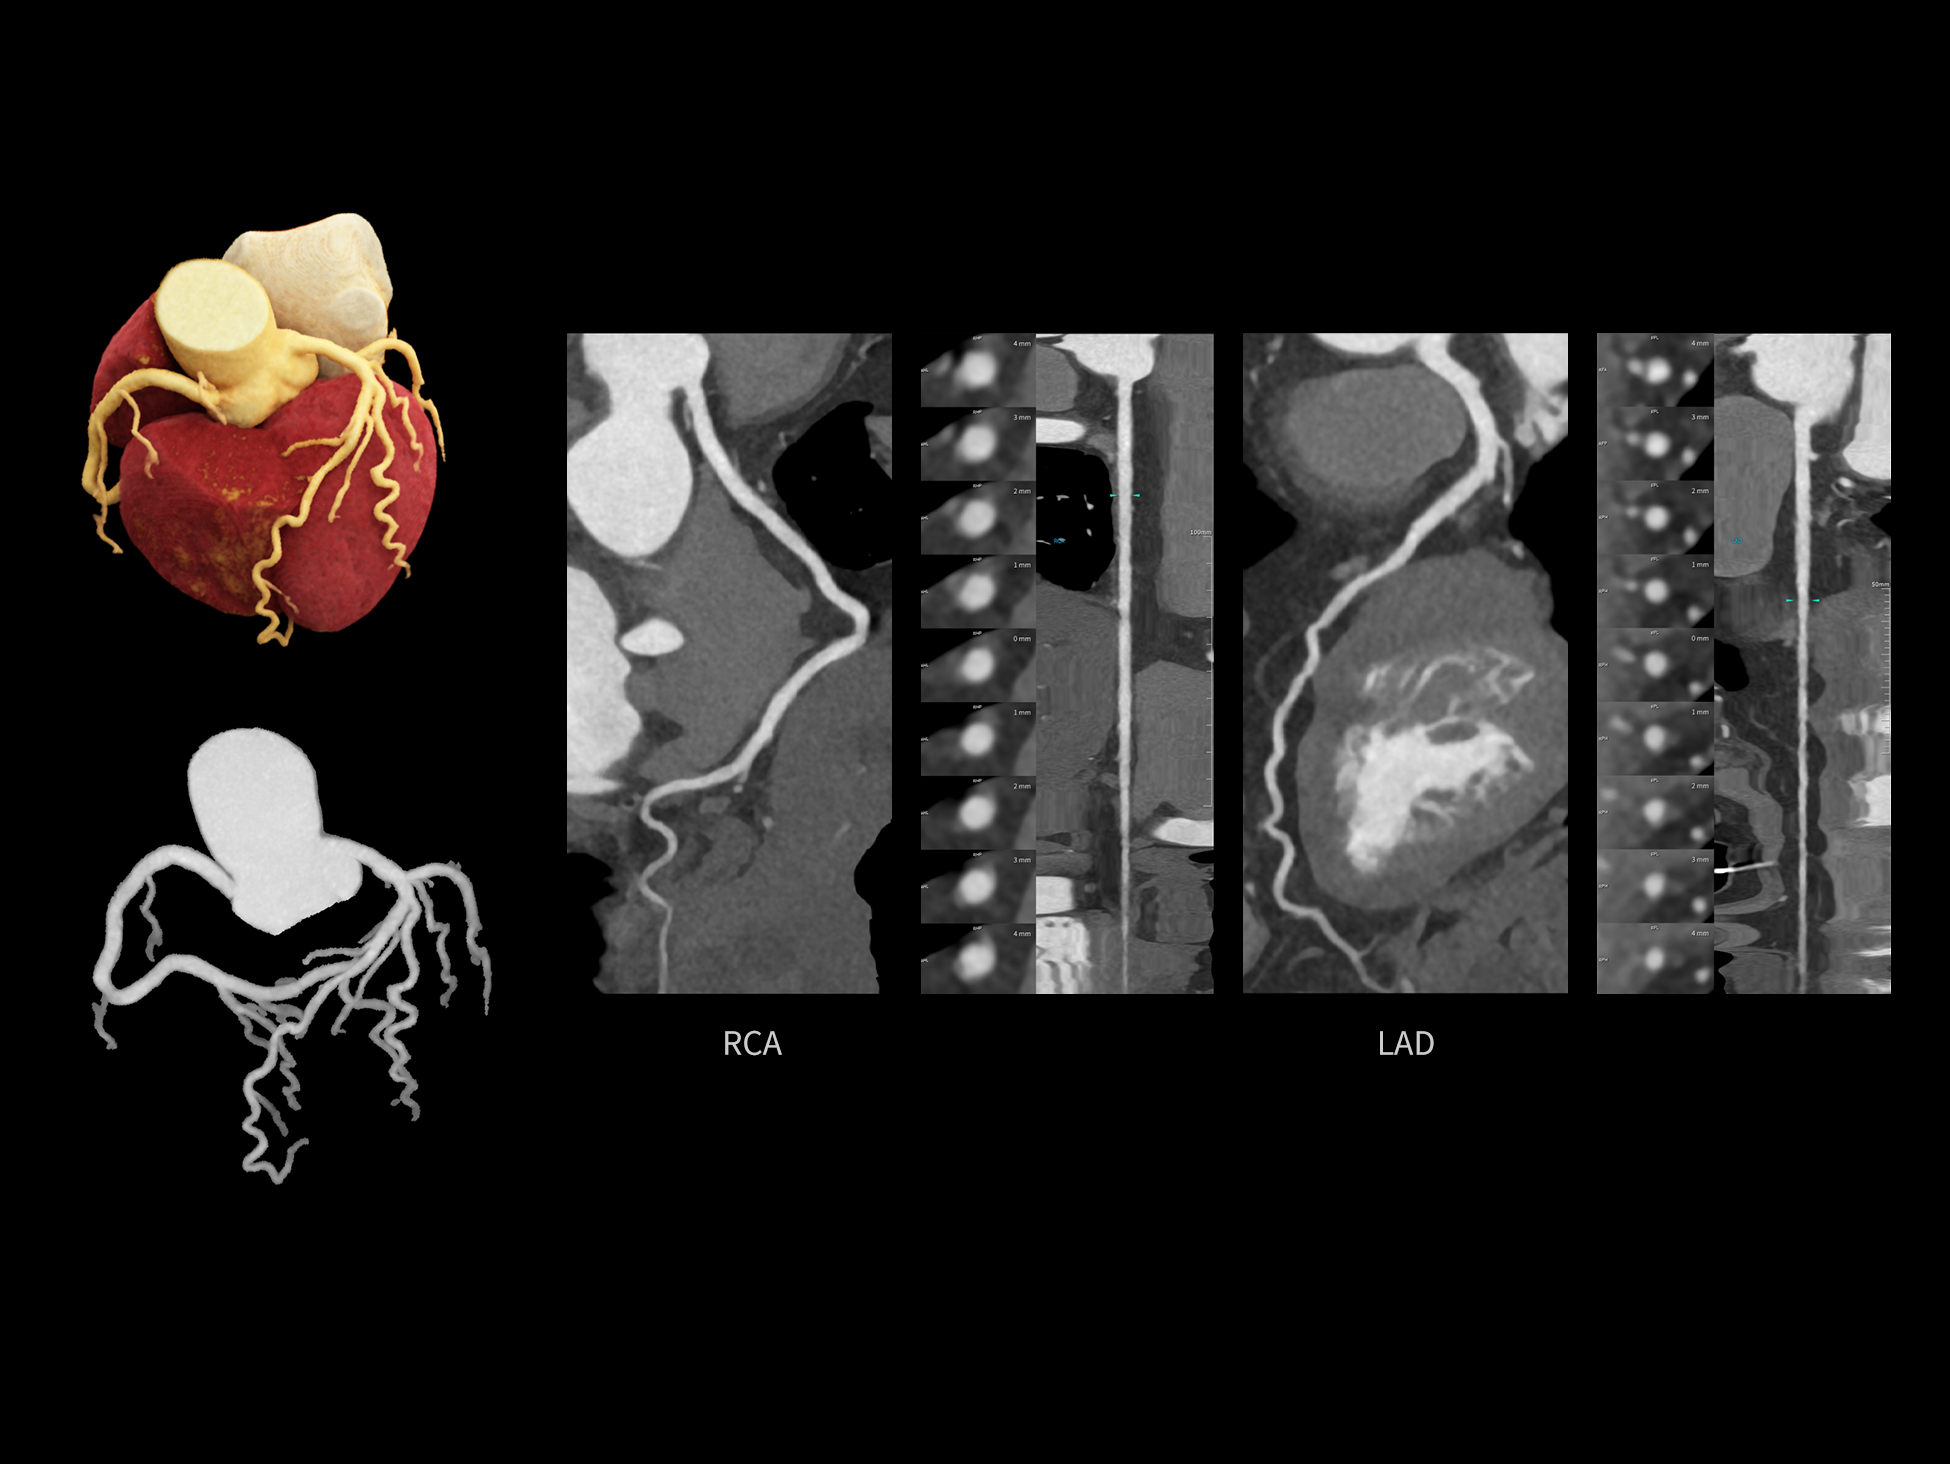

CardioCapture 2.0 通过“识别–追踪–建模–校正”的完整流程,精准分割心脏结构,动态追踪运动轨迹,并构建多时相运动场,最终实现冠脉、瓣膜、心肌及心室结构的同步校正,清晰洞见每一次心跳细微变化,真正将心脏动态掌握于毫秒之间。

CardioCapture 2.0 在目标时相前后重建多时相影像,通过深度学习网络精准提取冠脉中心线,进而建立时相间运动模型,实现对冠脉分段图像的精准运动校正。

冠脉运动校正

8ms 全心等效时间分辨率